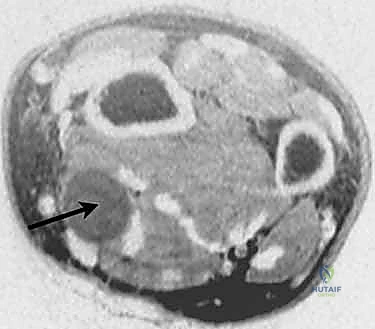

- التصوير بالرنين المغناطيسي (MRI): هو المعيار الذهبي (Gold Standard) لتشخيص أورام الأعصاب. يوفر صوراً عالية الدقة توضح حجم الورم، وموقعه الدقيق، وعلاقته بالعصب والأنسجة المحيطة (عضلات، أوتار، أوعية دموية). يمكن للرنين المغناطيسي التمييز غالباً بين ورم شوان والورم الليفي العصبي.

- الموجات فوق الصوتية عالية الدقة (High-Resolution Ultrasound): أداة ممتازة وديناميكية تتيح للطبيب رؤية الورم وتقييم تدفق الدم إليه.